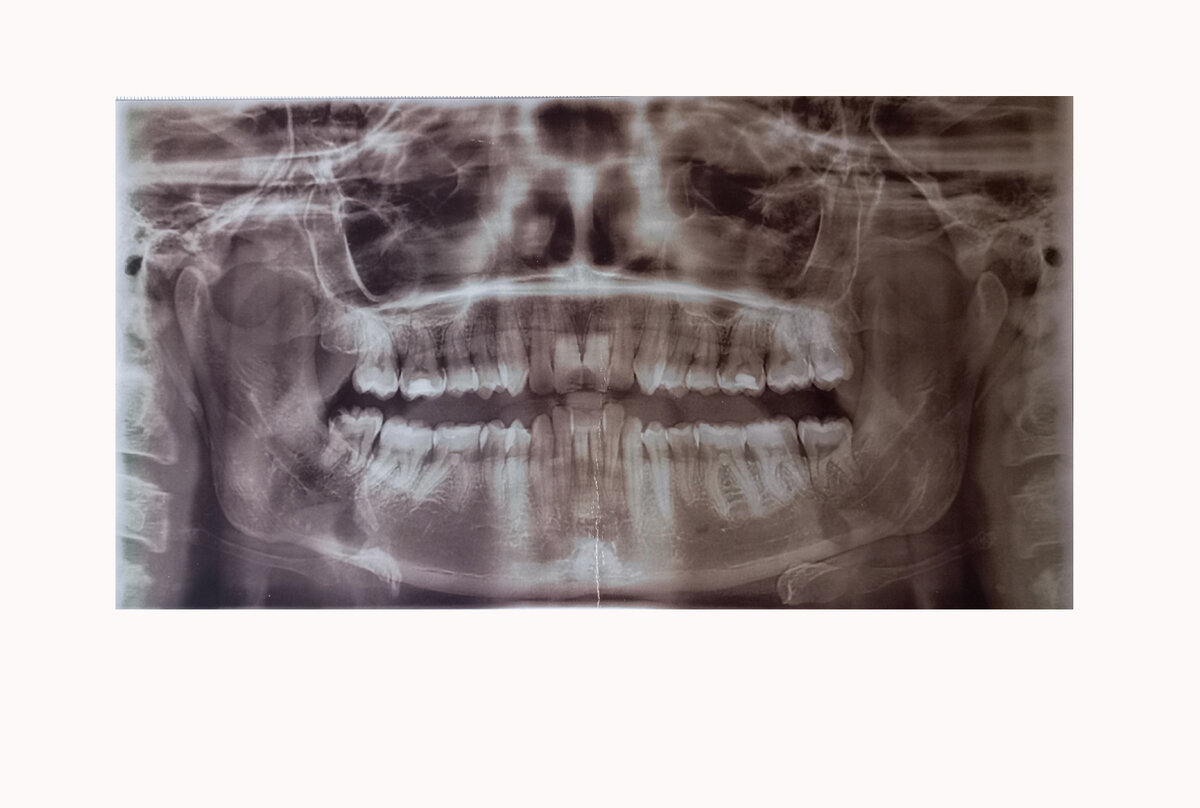

На примере зубов получилось очень показательно. Пять лет ежегодно хожу на чистку, зато нет кариеса. Удалены только восьмерки из-за брекетов, остальные на месте. Единственное, брекеты не избавили меня от клиновидных дефектов, а может даже поспособствовали их развитию, но тут никакой гарантии нет, тем более я была уже возрастным пациентом.

Зубы у меня самые обыкновенные, челюсть маленькая, типичная для коренных жителей болот Петербурга, но сейчас я чувствую себя уникальным экземпляром, умудрившимся сохранить к сорока семи годочкам все свои.

В моем случае, зубы красиво и ровно встали очень быстро, за несколько месяцев! В общей сложности я носила брекеты 2.5 года, как и обещали. Там уже шло идеальное выставление моляров и притирка жевательной поверхности.